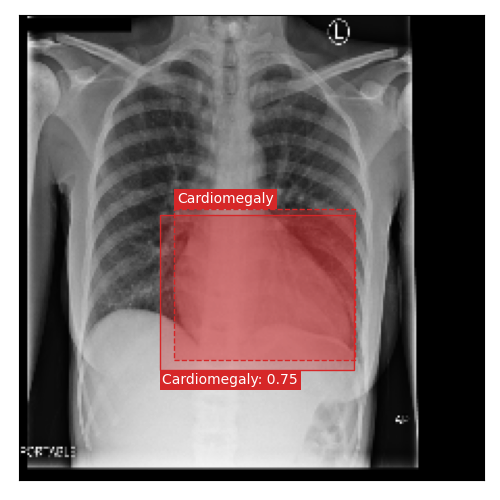

Qualitative Results

As shown in Fig. 4 Loc-ADPD detects cardiomegaly almost perfectly, as it is always exactly localized at one anatomical region. Other pathologies are detected but often with too large or too small boxes as they only cover parts of anatomical regions or stretch over several of them, which cannot be completely corrected using WBF. Detection also works well for predicting several overlapping pathologies. For qualitative comparisons between Loc-ADPD and MIL-ADPD, we refer to Appendix 0.B.